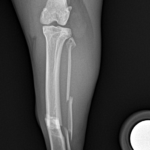

最小侵襲整形外科 脛骨を骨折した猫が足を痛がっているので手術して欲しいと主治医から連絡がありました。外科用イメージを使って、髄内ピンとプレートによる固定術を行い、翌日退院しました。この手法は皮膚や筋肉を大きく切開しないというメリットがあります。 症例カテゴリー 放射線治療整形外科軟部組織外科脳神経外科内科腫瘍外科救急・集中治療リハビリテーション科腫瘍内科内視鏡科脳神経科呼吸器外科中医・漢方猫の腎移植循環器科